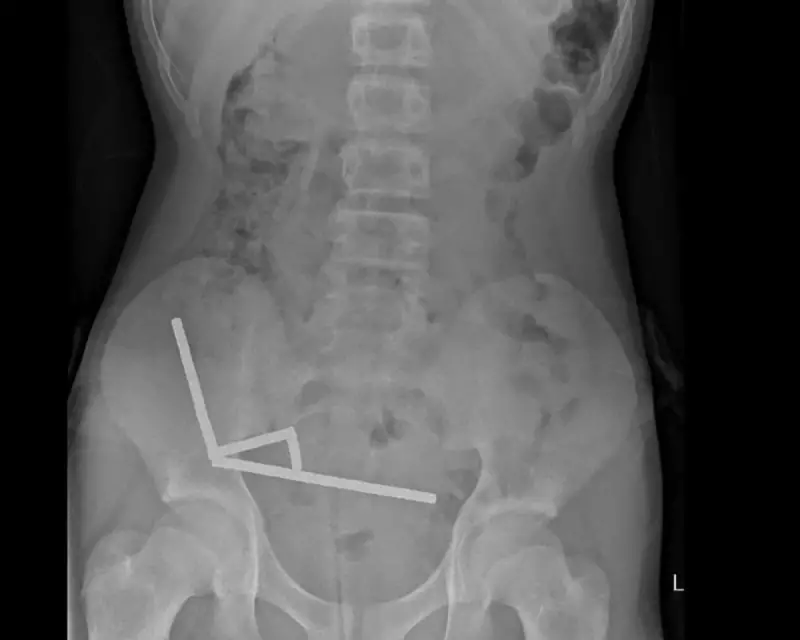

The case, reported by Wellington Hospital surgeons, involved a teen who had swallowed several rare-earth magnets purchased from the popular discount shopping platform Temu. These tiny but incredibly strong magnets, often marketed as "Buckyballs" or neodymium magnets, can create devastating internal injuries when multiple pieces are swallowed.

"When these powerful magnets separate inside the digestive system and then reconnect through intestinal walls, they essentially create a vice-like grip that cuts off blood supply," explained one medical professional familiar with the case.